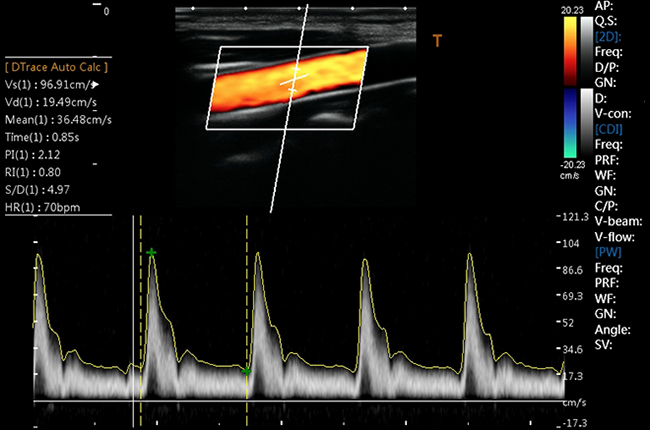

Кольорове допплерівське картування

Енергетичний допплерівський режим

Програма V-Flow - Векторний потік

Сонна артерія